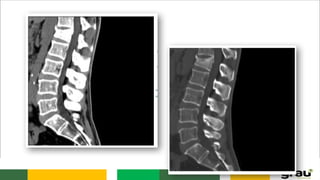

C. LOMBAR

5 vértebras (L1 a L5)

Corpo robusto

Processo espinhoso laminar

L2

L3-L4

C. LOMBAR 5 vértebras(L1 a L5) Corpo robusto Processo espinhoso laminar L2 L3-L4